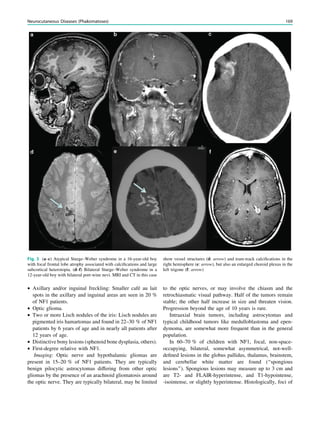

Tuberculosis, 210, 213

Index 269

Tuberous sclerosis, 138, 145, 165, 167

Type 1 lissencephalies, 132

Type 1, 131

Type 2A, 138

Type 2B, 138

Type I lissencephaly, 131

U